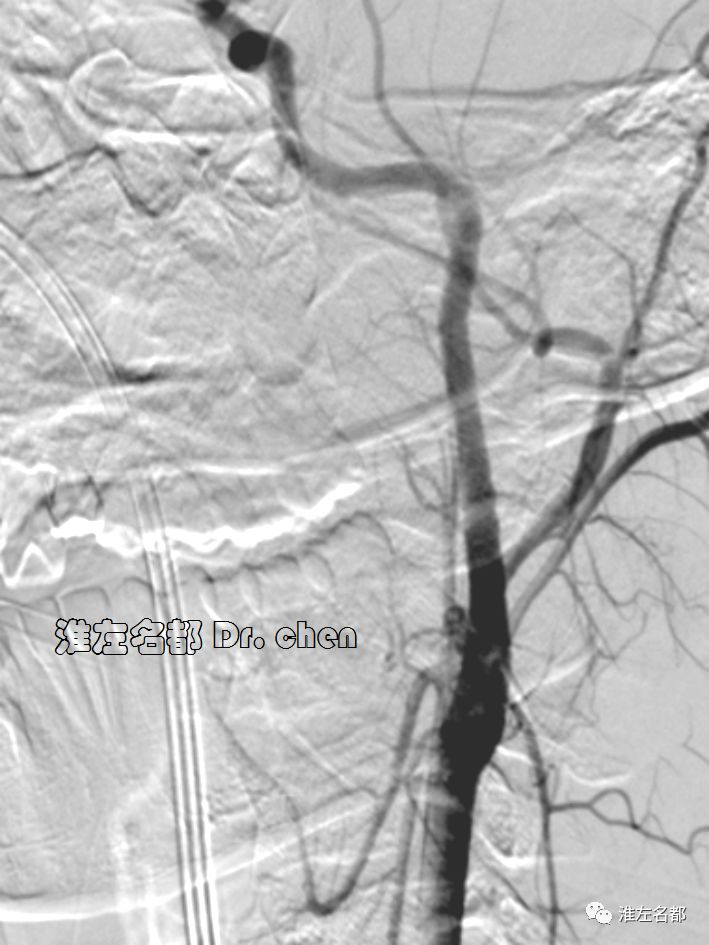

△经.035”泥鳅导丝将中间导管(Navien 058,125cm)送至左侧颈内动脉岩骨段,而后长鞘跟进至左侧颈内动脉,再经泥鳅导丝将中间导管送至海绵窦段,微导管(Rebar 27)在微导丝导引下进入左侧大脑中动脉M2段,造影证实位于真腔后,经微导管释放取栓支架(S AB 6*30mm)后造影:左侧颈内动脉远端充盈缺损,管腔严重狭窄;左侧大脑中动脉近端严重狭窄。

3.脑动脉夹层临床确诊依赖于影像学检测到典型夹层征象:内膜征/双腔征、长段不规则/丝线样狭窄、壁内血肿、夹层动脉瘤等。本患儿DSA显示左侧颈内动脉末端和大脑中动脉主干长段狭窄,且大脑中动脉主干狭窄呈“丝线样”,符合夹层影像学征象。

6.在夹层真腔得以基本恢复后,DSA于左侧颈内动脉末端、大脑前和中动脉近端均检测到典型“内膜征”,进一步确定了夹层诊断。